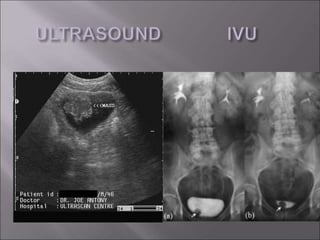

 ULTRASOUND

 INTRAVENOUS UROGRAM

 ULTRASOUND  INTRAVENOUSUROGRAM  CT SCAN  CYSTOSCOPY  URINE CYTOLOGY  ROUTINE INVESTIGATIONS